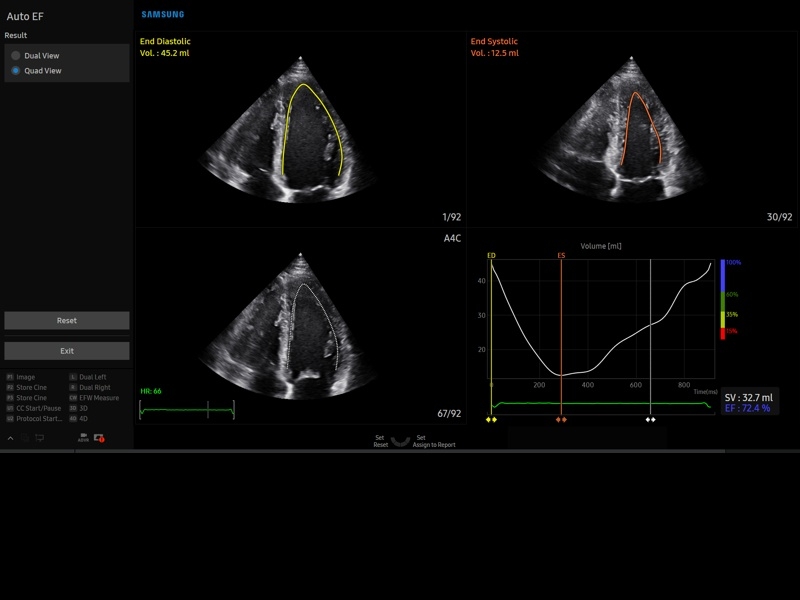

• Пакет кардиологических исследований.

М-режим:измерение диаметра аорты, передне-заднего размера ЛП, толщины МЖП (систолическая и диастолическая), толщины ЗСЛЖ (систолическая и диастолическая), размеров ЛЖ и ПЖ (систолический и диастолический), ФВ (Teichholz).

B-режим:измерение диаметра аорты (восходящей, дуги, нисходящей, на уровне синусов Вальсальвы, на уровне створок аортального клапана), определение размеров ЛП и ПП (максимальный, минимальный, систолический, диастолический, переднее-задний, верхнее-нижний, медиально-латеральный), расчет объемов ЛП и ПП, объемов ЛЖ (метод "Площадь-Длина", метод дисков (Simpson)), массы миокарда ЛЖ, индекса массы миокарда ЛЖ.

CD-режим (ЦДК):измерение радиуса ПФСМР (PISA), полуколичественная оценка трансмитрального, транстрикуспидального, трансаортального и транспульмонального кровотока (оценка регургитации), оценка аномальных сбросов крови через МПП И МЖП.

PW-режим (импульсно-волновой допплер):автоматическая, полуавтоматическая и ручная трассировка допплеровского спектра митрального, аортального и трикуспидального клапанов, клапана легочной артерии, кровотока в выходном тракте ЛЖ и ПЖ (пиковая/средняя скорость, пиковый/средний градиент давления, время изоволюметрического расслабления ЛЖ, время ускорения, замедления, выброса), оценка кровотока легочных и печеночных вен.

CW-режим (постоянно-волновой допплер):программы расчета работы митрального, аортального и трикуспидального клапанов, клапана легочной артерии.

TD-режим (тканевой допплер):количественная оценка локальной сократительной функции стенок ЛЖ и ПЖ.

• МодульStrain+- программа не векторной оценки степени сократимости миокарда с выведением автоматически расчетов и графиков на экране отдельно по каждому сегменту.

• Модуль Stress Echo – программа для исследования сердца под нагрузкой.